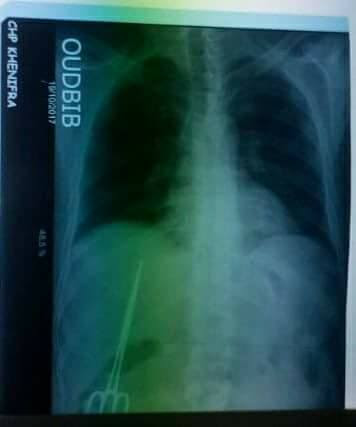

قالت جريدة اليوم 24 ، أن الطاقم الطبي بالمركز الاستشفائي بمدينة خنيفرة،كشف أمس الخميس، مقصا داخل القفص الصدري لرجل متقاعد، من المحتمل أن يكون عالقا منذ أزيد من 10 سنوات، تاريخ إجراء آخر عملية جراحية.

وحسب مصادر الجريدة ذاتها ، فإن المواطن “موحى. أ” الذي كان يتشغل ببلدية خنيفرة، عاودته الآلام المبرحة على مستوى صدره، فتوجه إلى المركز الاستشفائي، وبعد الفحوصات الأولية، تم إجراء الفحص بالأشعة، الذي أسفر عن مفاجأة لم تكن في حسبان الطبيب، حيث تبين له مقصا عالقا في القفص الصدري.

وزادت المصادر ذاتها أن المريض أوضح بأنه سبق له أن أجرى عملية جراحية بالمستشفى القديم لمدينة خنيفرة، قبل 10 سنوات، ويبدو أن الطبيب الجراح نسي مقصا داخل القفص الصدري للمريض الذي عانى طويلا من آلام في صدره، قبل أن يكتشف أمس السر وراء ذلك بالمركز الاستشفائي بخنيفرة.